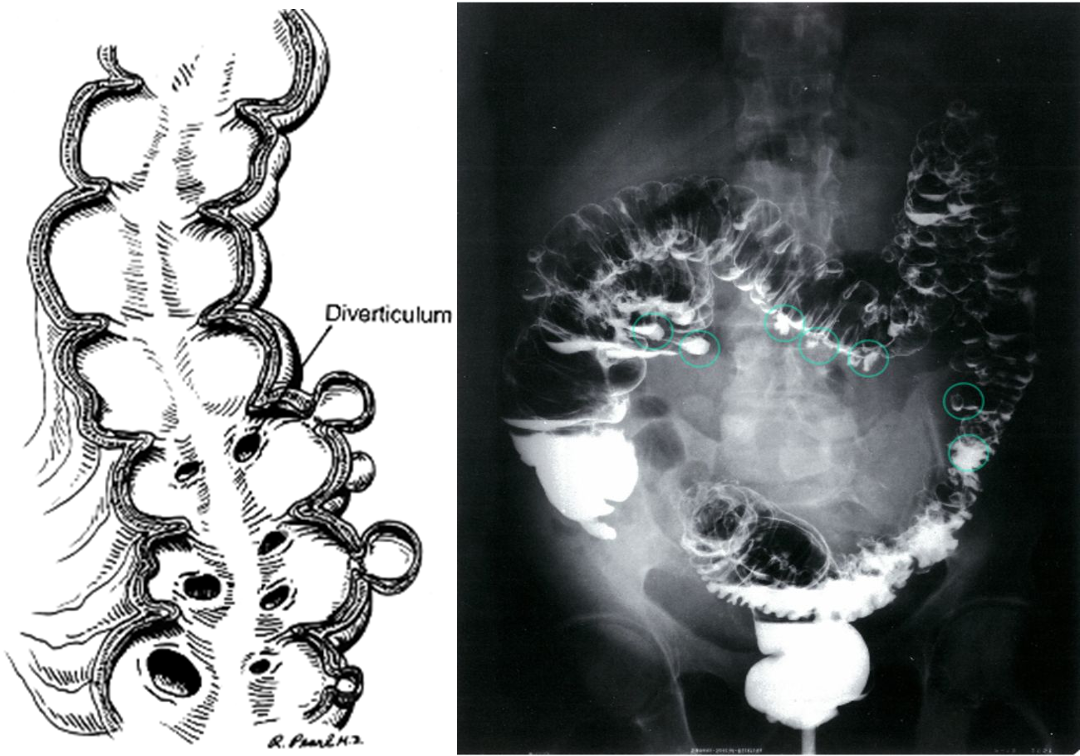

Diverticular disease. Small mucosal out pouching occur from the side large intestine.

Double-contrast barium enema: highly sensitive test to detect diverticulosis but not commonly performed

- Double-contrast barium enema of the colon

- Multiple diverticula in the colon can be seen (examples circled in green).